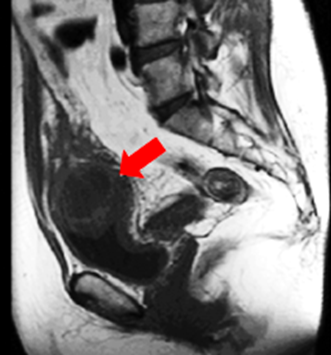

·         Magnetic Resonance Imaging (MRI): MRI offers excellent soft tissue contrast and can delineate the cyst’s boundaries, especially concerning surrounding tissue involvement or infection.